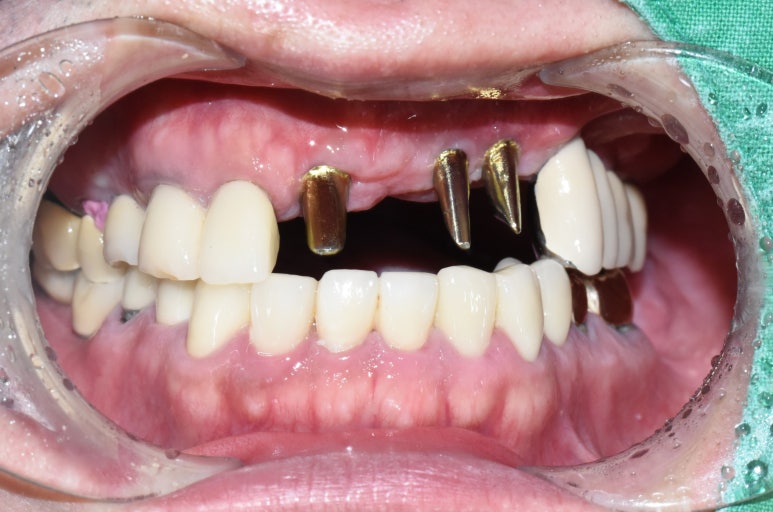

앞니 임플란트 진행중간 사진

어금니 임플란트와 앞니 임플란트를 하여

환자분이 편안한 식사생활과 사회활동을 할 수 있게 하였습니다.